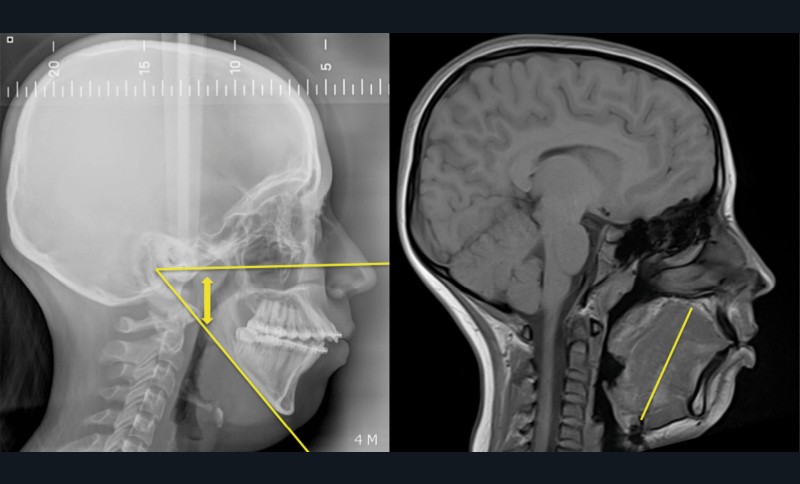

L’étroitesse squelettique peut également être impliquée (rétromandibulie, hyperdivergence, endognathie) [1] (fig. 1-4).

Plusieurs approches chirurgicales ont été décrites : les chirurgies des tissus mous visant la désobstruction pharyngée, les chirurgies squelettiques destinées à élargir le calibre pharyngé et, plus récemment, les interventions visant à augmenter le tonus musculaire lingual par stimulation du nerf hypoglosse (fig. 5).